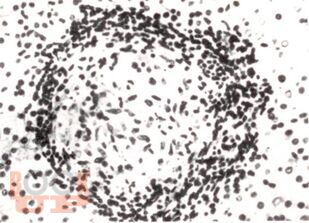

В учебно-методическом пособии авторы представили данные об этиологии, патогенез, патологической анатомии саркоидоза, клинико-рентгенологические классификации, методы диагностики лабораторные, лучевые (рентгенография, томография, КТ, МРТ, ПЭТ), радиоизотопное, бронхологические особенности современного саркоидоза. Приведены примеры собственных наблюдений.